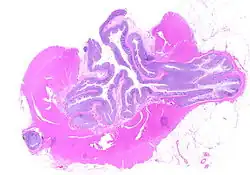

The precise mechanisms by which diverticula are formed are unknown.[1] Multiple theories have been proposed including genetic susceptibility, diet, intestinal motility, changes in the microbiome, and inflammation. One leading theory suggests that diverticula form in weakened areas of the colon wall that are subjected to increased pressure.[1] The strength of the colon wall is known to decrease with age.[1] Previous theories proposed that impacted fecal matter and certain foods would get stuck in diverticula (thereby causing trauma), which caused poor blood flow, death of the affected intestinal wall cells, and intestinal perforation.[1] Newer theories have called this paradigm into question.[1]

Pathophysiology